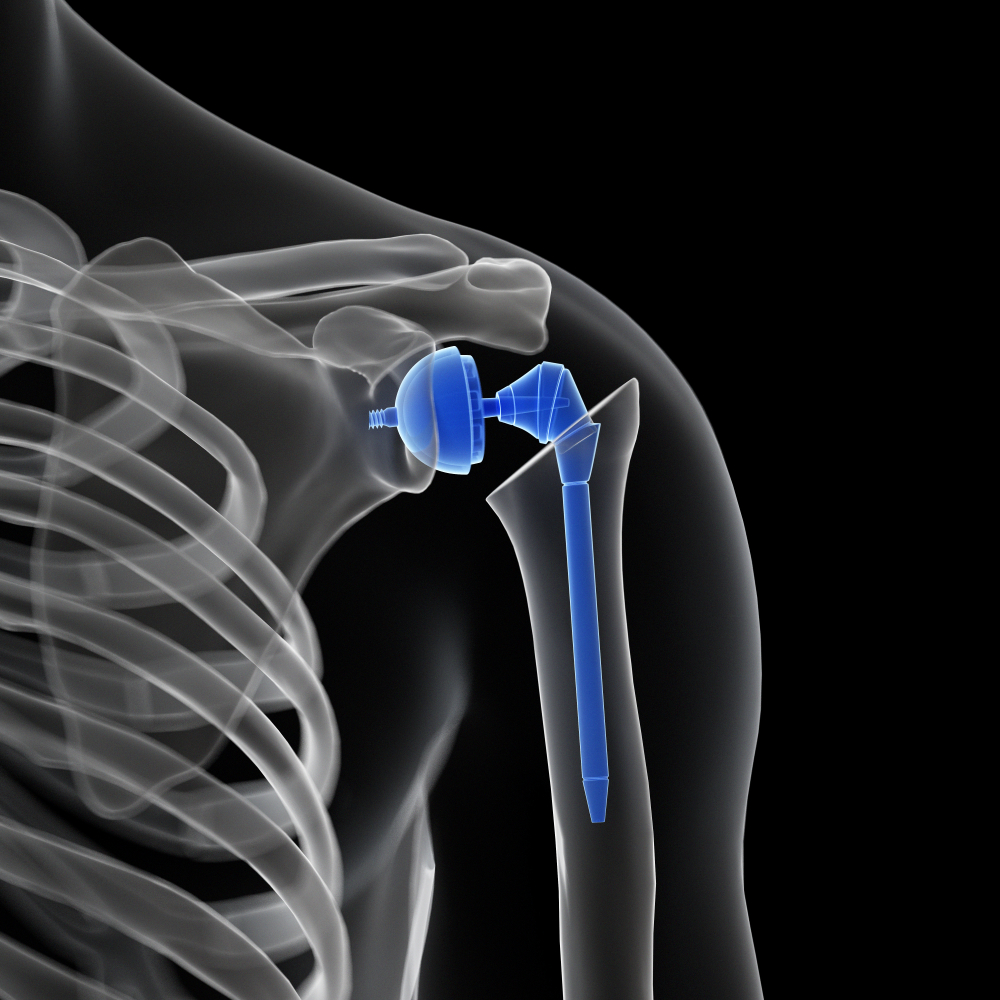

Debido al desgaste de la articulación del hombro en ocasiones se debe recurrir a una cirugía de reemplazo de la articulación, por una artificial conocida como prótesis de hombro con partes de metal y plástico.

El hombro es una enartrosis lo cual quiere decir que el extremo redondo del hueso del brazo encaja dentro de la abertura en el extremo del omóplato. Este tipo de articulación permite mover el brazo en la mayoría de las direcciones.

Para el reemplazo total del hombro, el extremo redondo del hueso del brazo se reemplazará con una caña o vástago artificial que tiene una cabeza de metal redondeada. La parte de la cavidad (glenoide) del omóplato se reemplazará con una cubierta plástica y lisa (recubrimiento) que se sostendrá en el lugar con un cemento especial. Si sólo 1 de estos 2 huesos necesita ser reemplazado, la cirugía se denomina artroplastia parcial del hombro o hemiartroplastia.

Extraerá la cabeza (epífisis) del hueso de la parte superior del brazo (húmero).

Fijará con cemento la nueva cabeza y vástago de metal en el lugar.

Aplanará la superficie de la cavidad y fijará con cemento la nueva cubierta en el lugar.

El hombro es una enartrosis lo cual quiere decir que el extremo redondo del hueso del brazo encaja dentro de la abertura en el extremo del omóplato. Este tipo de articulación permite mover el brazo en la mayoría de las direcciones.

Para el reemplazo total del hombro, el extremo redondo del hueso del brazo se reemplazará con una caña o vástago artificial que tiene una cabeza de metal redondeada. La parte de la cavidad (glenoide) del omóplato se reemplazará con una cubierta plástica y lisa (recubrimiento) que se sostendrá en el lugar con un cemento especial. Si sólo 1 de estos 2 huesos necesita ser reemplazado, la cirugía se denomina artroplastia parcial del hombro o hemiartroplastia.

Extraerá la cabeza (epífisis) del hueso de la parte superior del brazo (húmero).

Fijará con cemento la nueva cabeza y vástago de metal en el lugar.

Aplanará la superficie de la cavidad y fijará con cemento la nueva cubierta en el lugar.